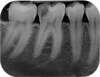

Radio dentaire